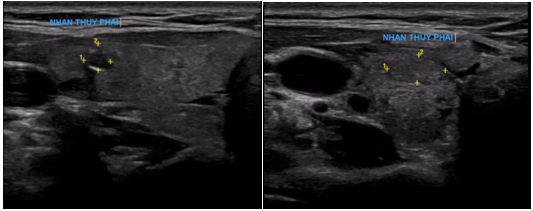

Ca lâm sàng: Điều trị thành công bệnh nhân ung thư tuyến giáp đã di căn xương cột sống sau 16 năm tại Trung tâm Y học hạt nhân và Ung bướu

GS.TS. Mai Trọng Khoa, PGS.TS. Phạm Cẩm Phương, Ths Lê Quang Hiển, BS. Vũ Thị Huyền Trung tâm Y học hạt...